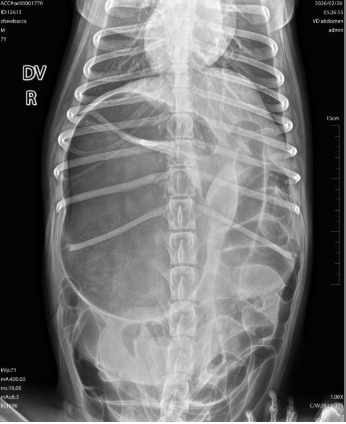

Smokey es más que una mascota, es mi familia. Desde el 5 de marzo, hemos estado viviendo una pesadilla. Lo que empezó como un vómito constante terminó en un diagnóstico crítico: vólvulo gástrico (estómago torcido).